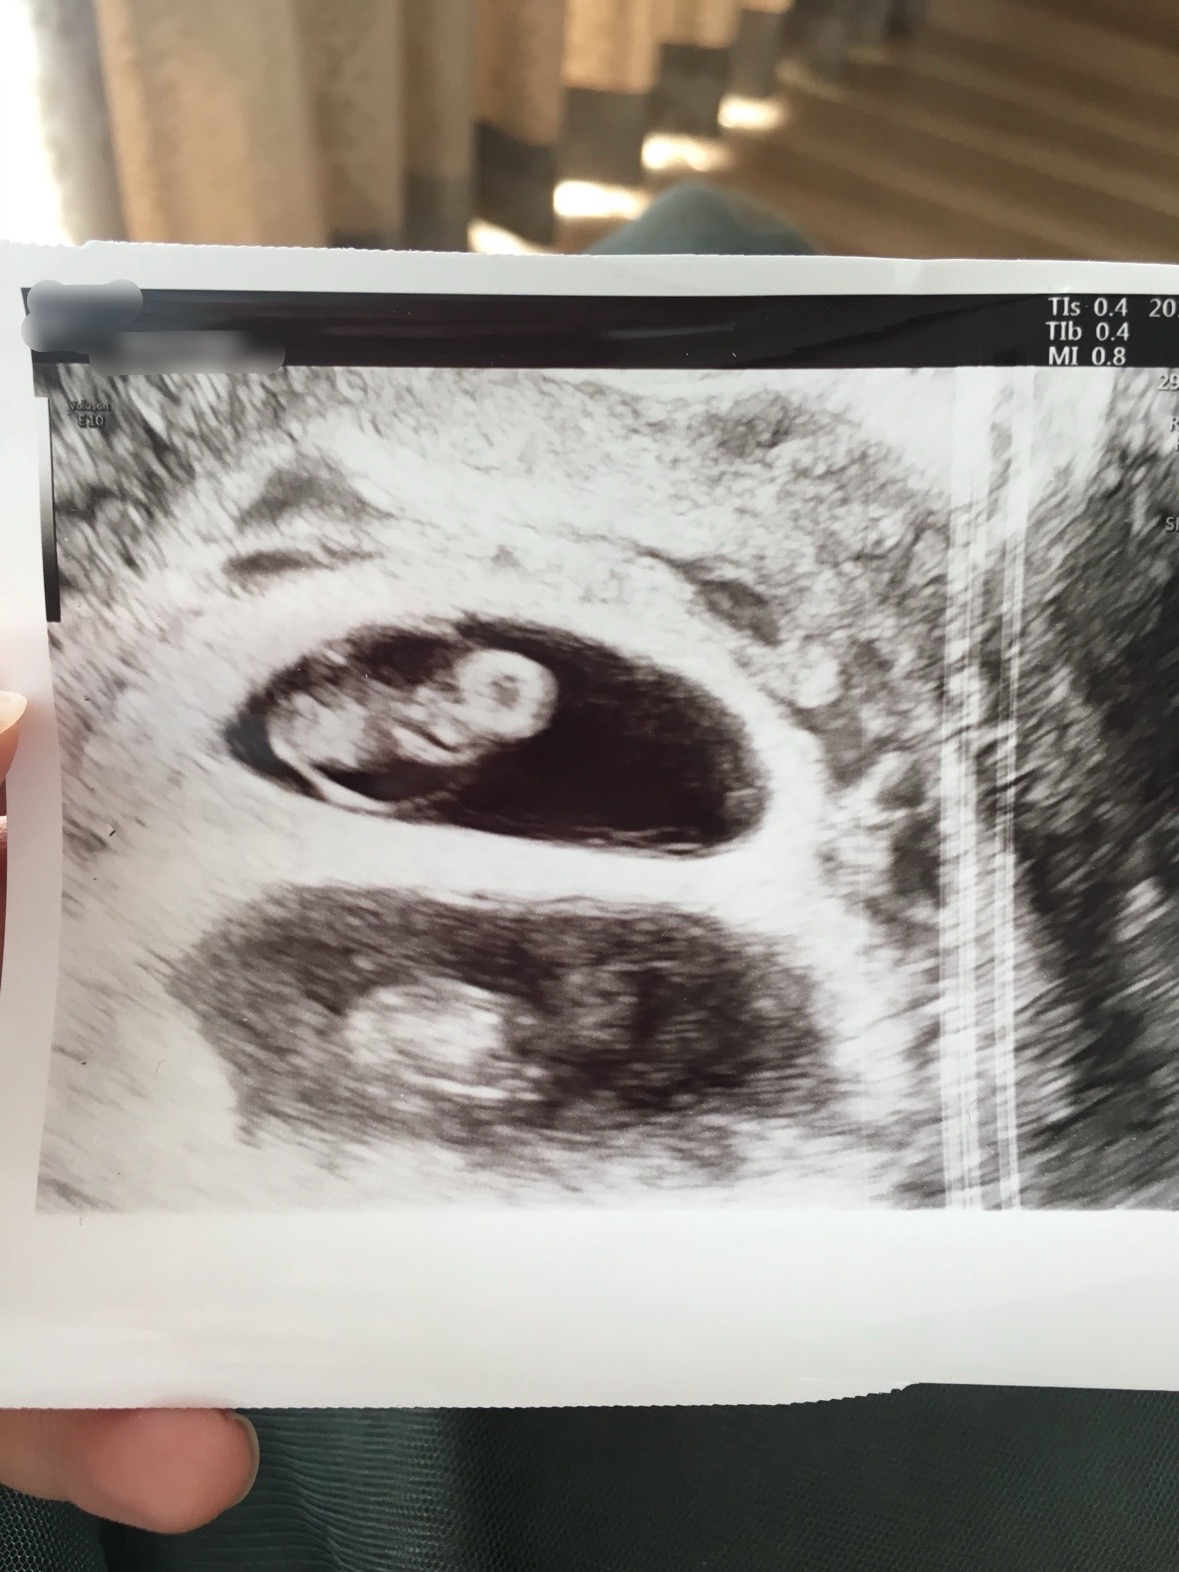

最初に双子と聞いたのは妊娠初期の検診でした。不妊治療専門の産婦人科で妊娠前から検診を受けており、排卵誘発剤を服用しての妊娠だったため「多胎の可能性」を全く考えなかったわけではありませんでした。それでもエコーで「胎のうが2個みえますね」と言われたときにはさすがにプチパニックでした。私も一緒にエコー画面を見て、2つの胎のうをしっかりと確認しました。